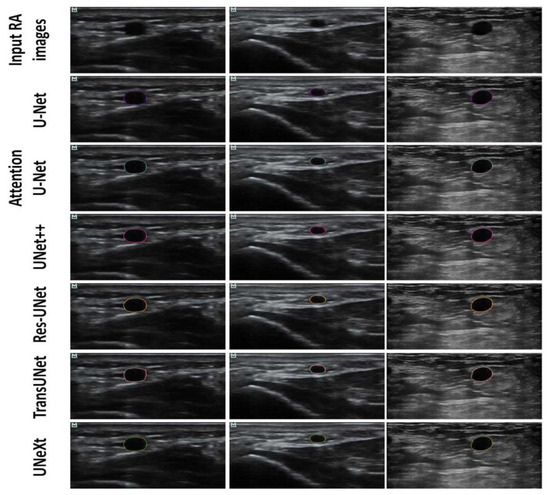

DSC (%) | JSC (%) | |

---|---|---|

Res-UNet | 93.14 ± 3.58 | 87.93 ± 5.57 |

U-Net++ | 91.98 ± 6.31 | 86.08 ± 8.88 |

U-Net | 91.79 ± 8.51 | 86.19 ± 10.02 |

UNeXt | 91.33 ± 5.16 | 84.94 ± 7.93 |

Attention U-Net | 91.20 ± 7.49 | 85.02 ± 10.17 |

TransUNet | 91.08 ± 7.02 | 84.88 ± 9.48 |